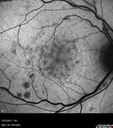

56 year old woman About 1 month ago the vision in the right eye went bad a few times and then got better. Then 1 week ago the vision in the right eye went bad again and has not gotten any better. Left eye is OK. The vision in the right eye is hazy and blurred. She has high blood pressure. She had a carotid ultrasound a week ago which showed some stenosis in the left which will be repeated. She has an echocardiogram scheduled and she has a neurology appointment coming up because of the vision loss last week. She had an episode where she passed out a few times and was recommended to take aspirin. She was told it might be dehydration. She was given a big long name of what was causing it. She has 2 children and had one miscarriage. She has had thyroid cancer.

VA 20/160 OD, 20/32 OS - Blood test showed hyperhomocysteinemia

CRVO with Paracentral Acute Middle Maculopath - PAMM664 views56 year old woman with sudden vision loss, hemorrhages in all four quadrants. FA shows good retinal circulation. The OCT shows PAMM lesions in the affected eye. Vision did improve on second visit from 20/160 to 20/60 in about a month     (0 votes)